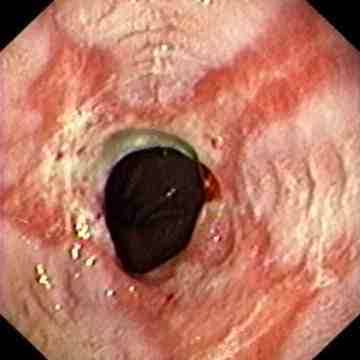

Reflux oesophagitis grade D according to the Los Angeles classification